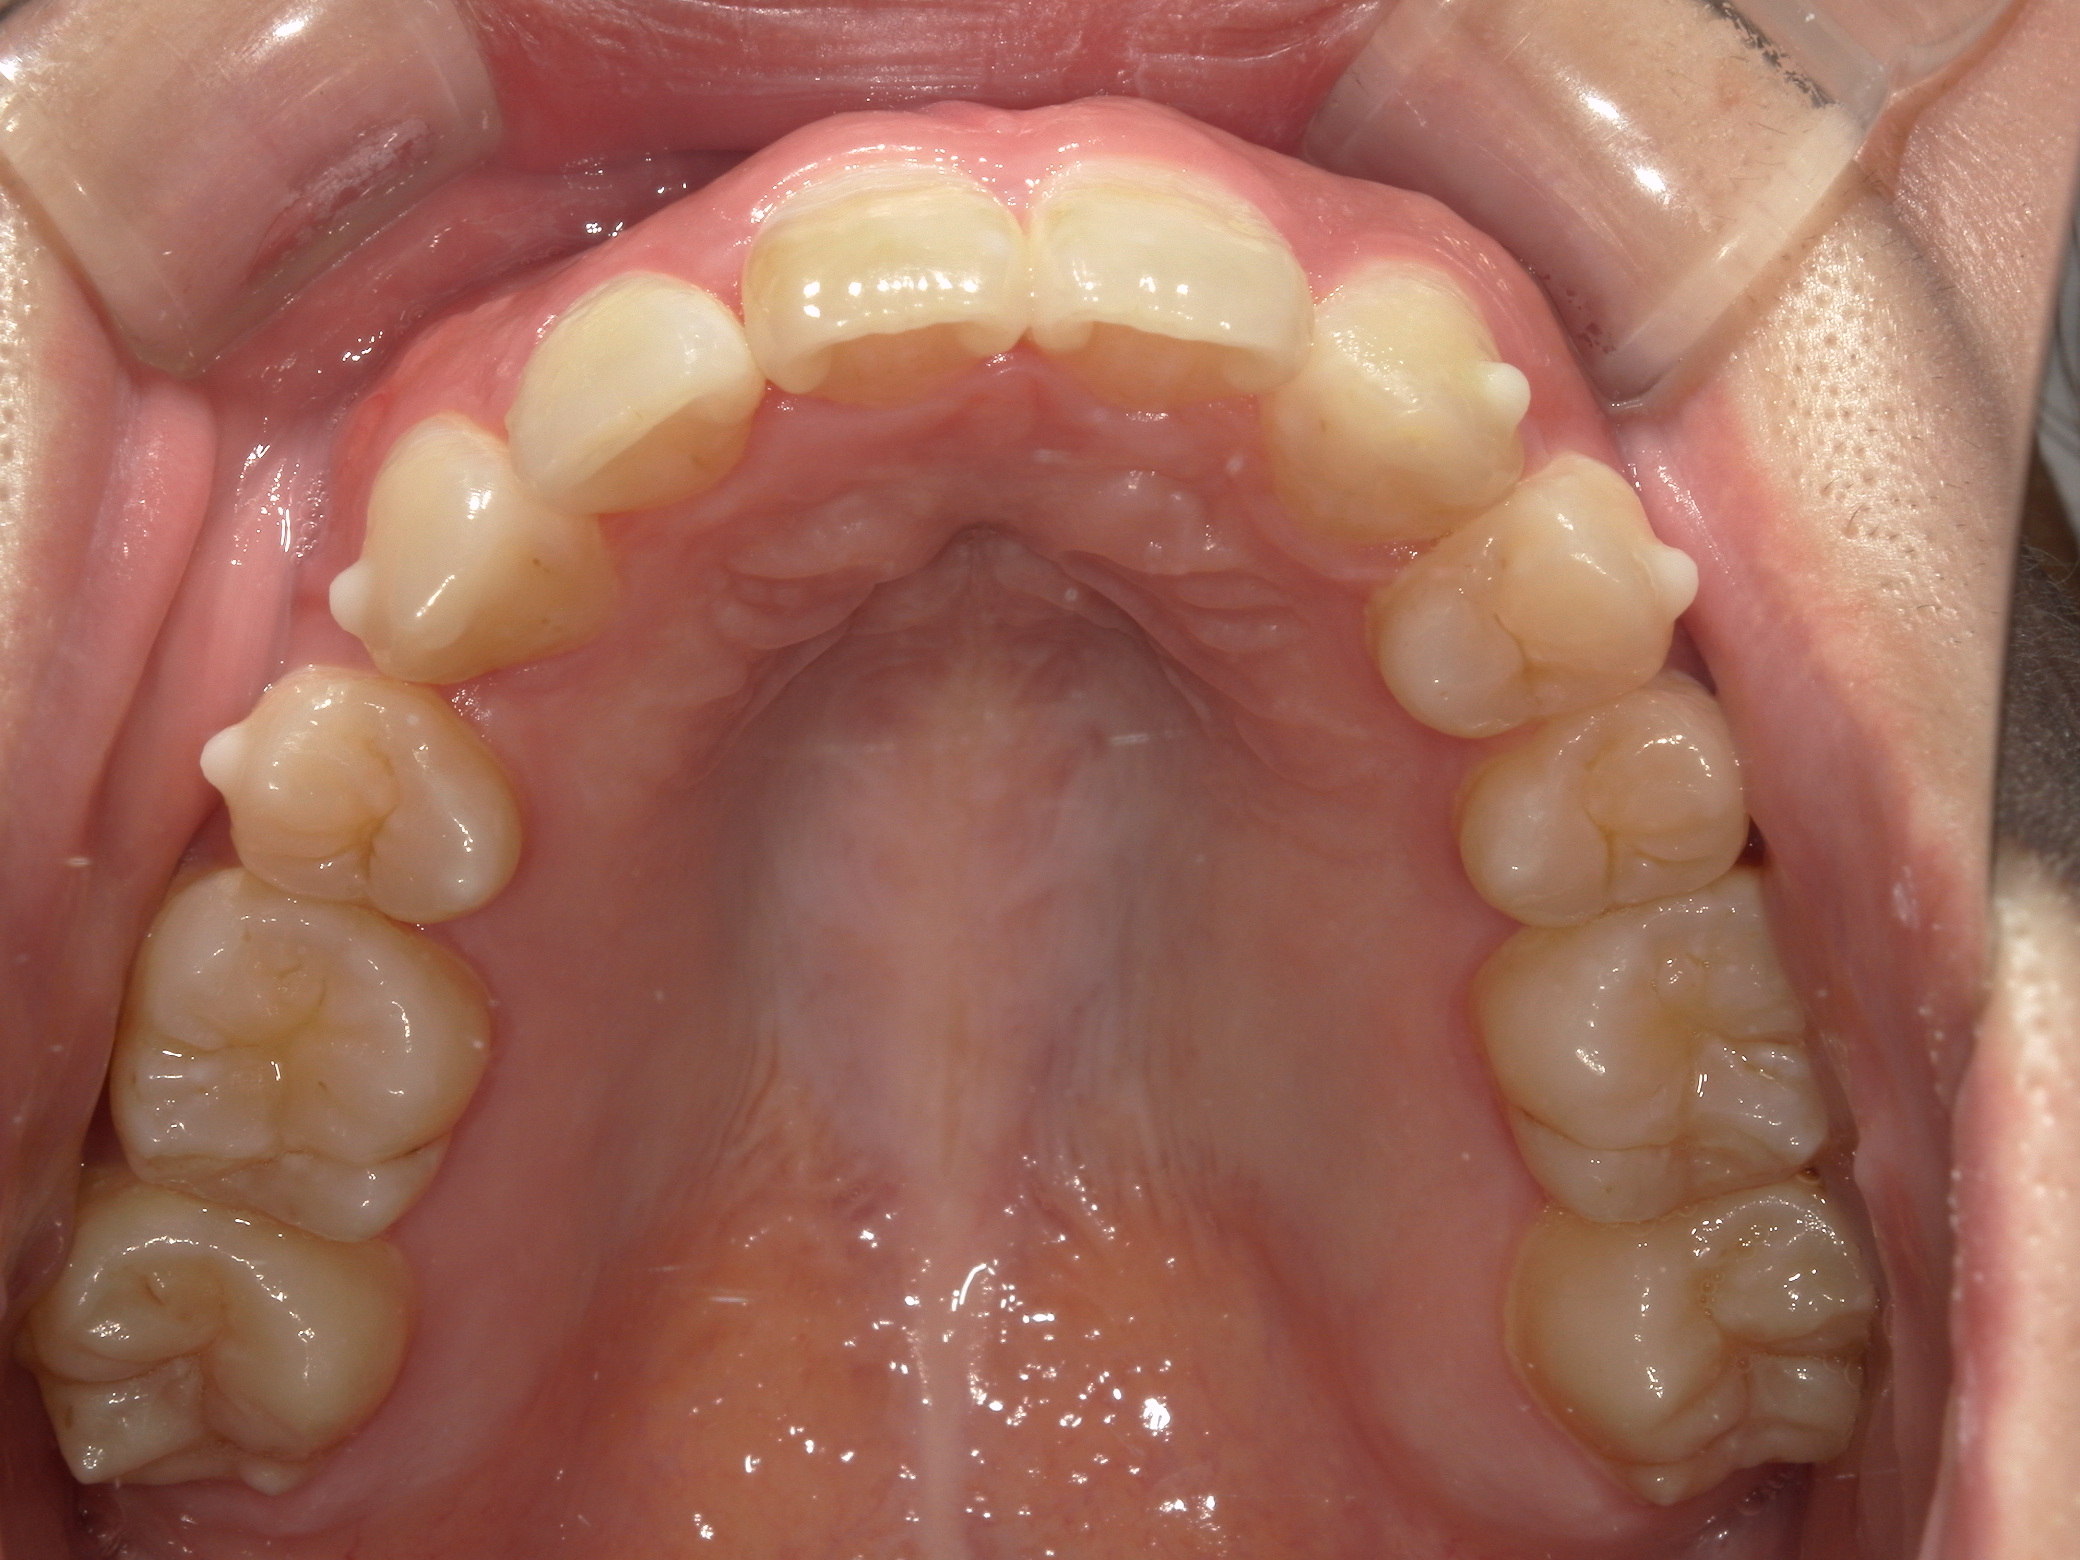

叢生が気になる

| 年齢・性別 | – |

|---|---|

| 主訴 | 叢生が気になる |

| 治療期間・回数 | 1年9ヶ月 |

| 費用 | 1,011,000円 |